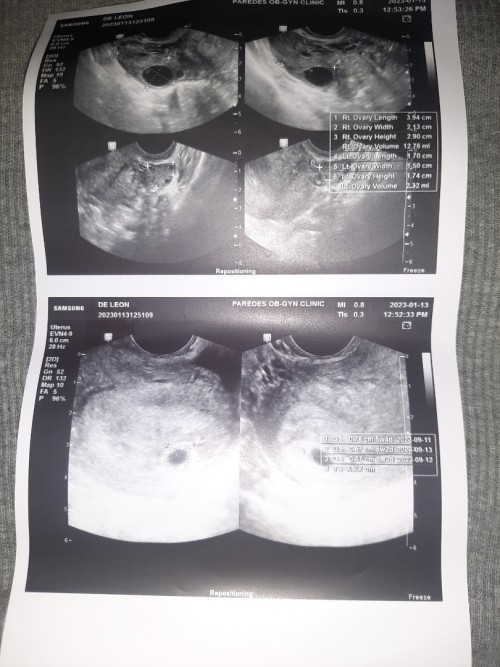

Ultrasounds Results LMP : 12/10/2022 Mga momshie’s, nagpa ultrasound ako last December 30,2022 to check if may pcos pa ako pero ang nakita is (Gastational sac like focus within) and it consider early sign of pregnancy pero may PCOS parin naman. Pinag take ako ng ob ko ng pregnancy test kinabukasan December 31 ng morning pero negative padin so she advised me po na bumalik after 2 weeks so January 13,2023 ngayon po pero bago daw ako pumunta mag take ako ng pregnancy test and faint line to positive po ang lumabas pagka ultrasound sakin ang nakita naman po is No Gastational sac seen, possible po kaya na ganun ang maging result? Meron nung una pero nung ngayon wala na po pero positive ang PT? Please respect my post, first baby ko palang po ito if ever hehe thank you so much! God bless ❤️

4W1D

Ultrasound Result

LMP: 12/10/2022